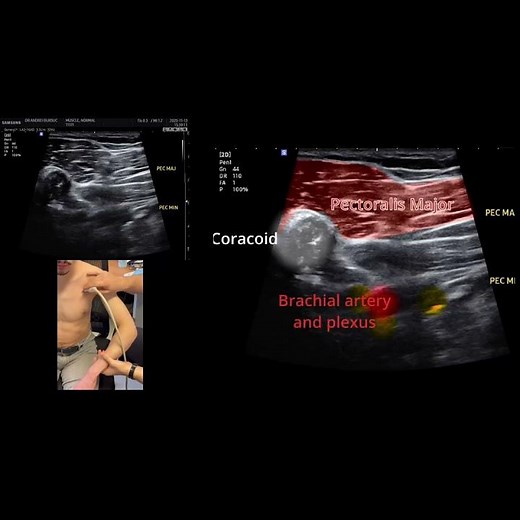

Petit Pectoral - PEC

Scapula - Pectoralis

Archaiques - Pectoralis

Musculaire - Pectoralis Minor